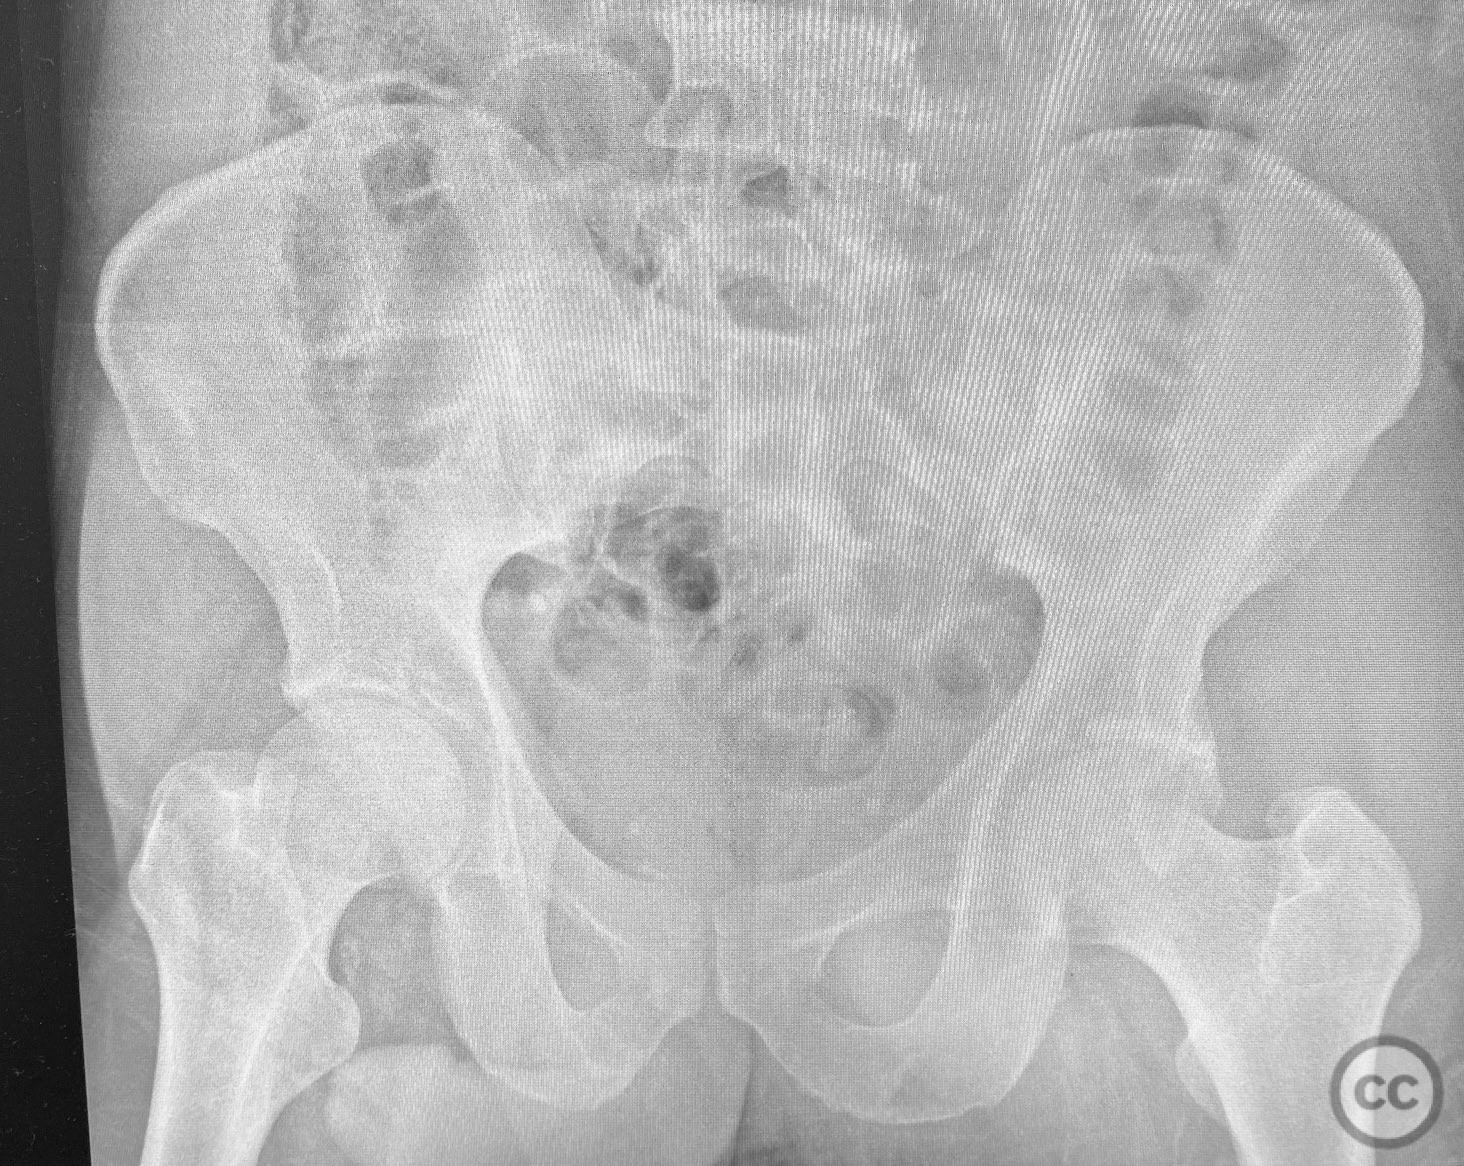

Acetabulum - AO/OTA 62x